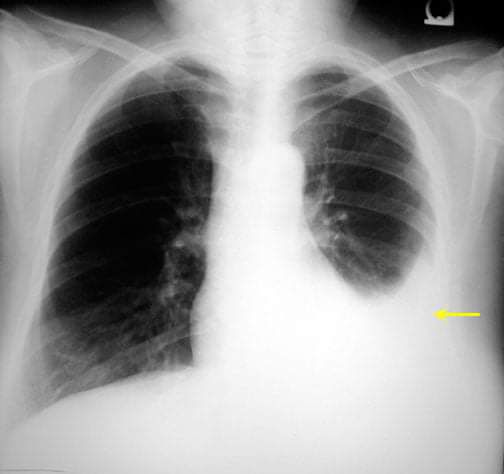

What's your diagnosis?

Plural effusion

Pleurisy or pleural effusion

Pleural effusion